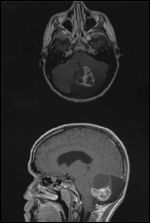

FIGURE 4

Medulloblastoma

• Medulloblastoma-Medulloblastoma is the most common malignant brain tumor in children. About 400 children are diagnosed with this tumor each year in the United States.[1] The peak age of onset is between 5 and 9 years. Over 90% of medulloblastomas typically arise from the superior medullary velum, growing to fill the cavity of the fourth ventricle (Figure 4).[33] The tumor mass can encroach on to the cisterna magna and sometimes infiltrates the floor of the fourth ventricle or brain stem. A minority of tumors, particularly in patients over 16 years of age, arise more laterally in the cerebellar hemispheres.[33] Macroscopically, these tumors are soft, friable, and moderately demarcated from the cerebellar tissue. Areas of central necrosis may be present.